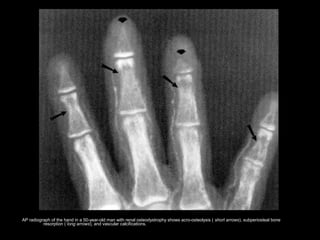

• Subperiosteal resorption - M/C

– Usually occurs in the hands and feet.

– M/C affected site: radial aspects of the middle phalanges.

– Acro-osteolysis or phalangeal tufts resoption may also be

present.

AP radiograph of the hand in a 50-year-old man with renal osteodystrophy shows acro-osteolysis ( short arrows), subperiosteal bone

resorption ( long arrows), and vascular calcifications.